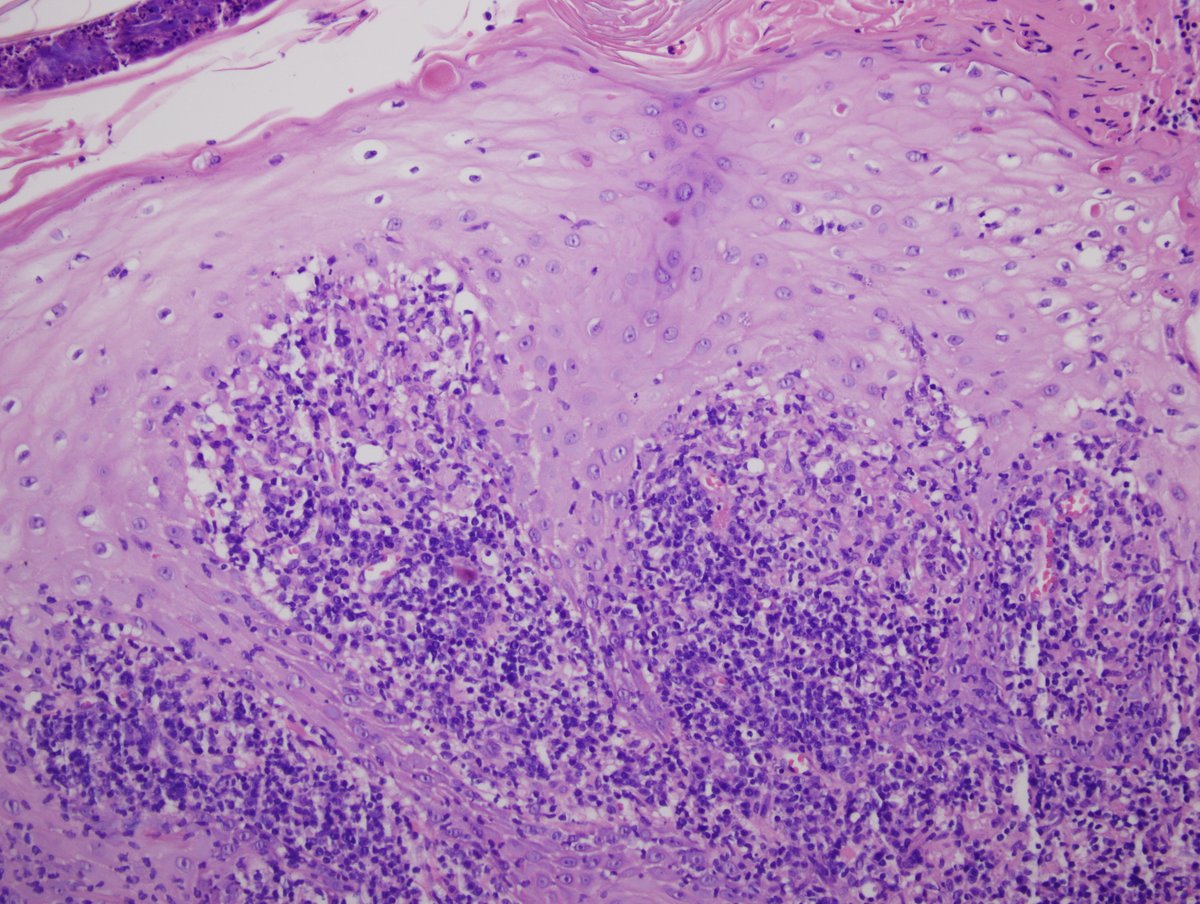

A nice case of a 13 yrs old female with ulcerated skin papules on the face.

#dermatology#pathology Dx: Leishmaniasis. Transmission: Sandflies. pic.twitter.com/RoxDn9UY1W